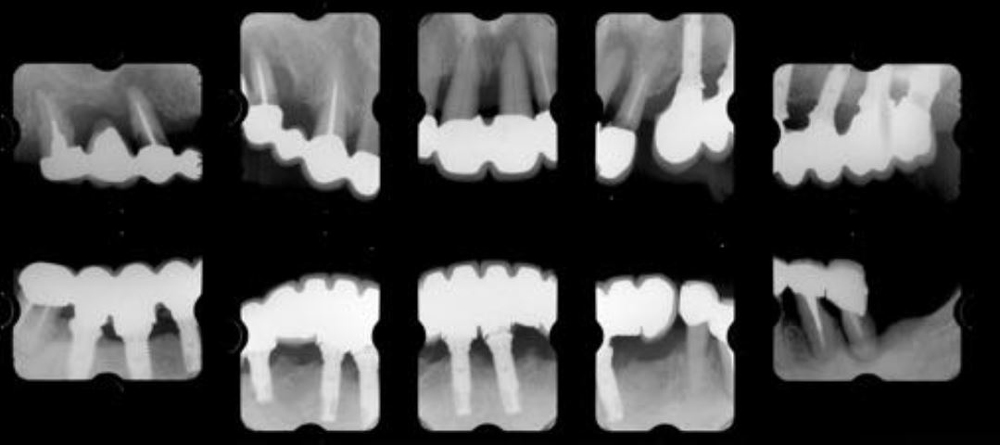

治療前01

治療前02

治療前03